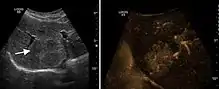

It is the most common liver tumor with a prevalence of 0.4 – 7.4%. It is generally asymptomatic but also can be associated with pain complaints or cytopenia and/or anemia when it is very bulky. It is unique or paucilocular. It can be associated with other types of benign liver tumors. Characteristic 2D ultrasound appearance is that of a very well defined lesion, with sizes of 2–3 cm or less, showing increased echogenity and, when located in contact with the diaphragm, a "mirror image" phenomenon can be seen. When palpating the liver with the transducer the hemangioma is compressible sending reverberations backwards. Doppler exploration reveals no circulatory signal due to very slow flow speed. CEUS investigation has real diagnosis value due to the typical behavior of progressive CA enhancement of the tumor from the periphery towards the center. The enhancement is slow, during several minutes, depending on the size of hemangioma and on the presence (or absence) of internal thrombosis. During late (sinusoidal) phase, if totally "filled" with CA, hemangioma appears isoechoic to the liver. Deviations from the above described behavior can occur in arterialized hemangiomas or those containing arterio-venous shunts. In these cases, differentiation from a malignant tumor is difficult and requires other imaging procedures, follow up and measurements of the tumor at short time intervals.[4]